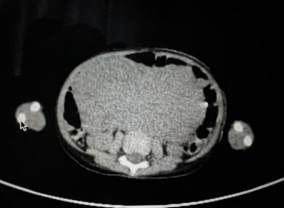

Figure 1, 2

On Imaging CECT abdomen suggestive of a Large soft tissue density heterogeneous mass lesion 127x8.3 x 11.1 in the central abdomen with lobulated margin and degeneration. No calcification is noted. As the origin of the mass and diagnosiscould not be made on imaging, a core needle biopsy was done from a mass lesion.

Figure 1

Figure 2